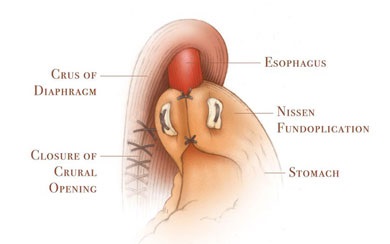

Scopul interventiei chirurgicale este de a restabili bariera antireflux, fără a crea obstacole în calea bolului. Nissen fundoplicatură - chirurgie antireflux, în care folie gastric în jurul părții inferioare a esofagului 360 °. creând o manșetă care previne conținutul gastric în esofag. Inainte de operatie, pacientii ar trebui sa fie examinate cu atenție, o atenție deosebită trebuie acordată la ultimul etaj al radiografiei tractului gastro-intestinal pentru a exclude alte posibile boli.

Principalele etape ale fundoplicatură Nissen:

- creând un drum liber Nissen înălțime manșetă de 1 - 2 cm;

- fixarea manșeta la esofag și piciorul drept al diafragmei;

- excizia sacul herniei și suturarea diafragmei la picioarele HH.

Manșetă Nissen reticulat pe două rânduri sutura.

Creați gratuit înălțimea Manșetă Nissen de 1 - 2 cm